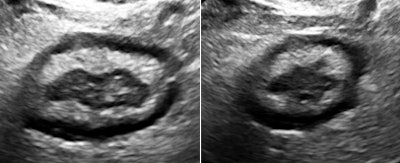

![]() |

The findings in these views of the distal descending left colon are typical and classic for active ulcerative colitis. The submucosa is thick, reflective, and hyperemic. Some divots can be seen along the mucosa and one transverse section shows a tiny submucosal cyst. What do you think a transabdominal exam would have shown? Would that study have served the best needs of this patient?